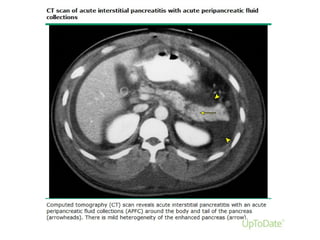

Interstitial edematous pancreatitisInterstitial edematous pancreatitis

The majority of patients with AP have diffuse (or occasionally localised)

enlargement of the pancreas due to inflammatory oedema. (75-80% )

On CECT, the pancreatic parenchyma shows

relatively homogeneous enhancement, and the peripancreatic fat usually

shows some inflammatory changes of haziness or mild stranding.

There may also be some peripancreatic fluid .

The clinical symptoms of interstitial oedematous pancreatitis usually

resolve within the first week.